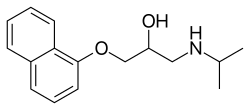

Currently, the available pharmacological therapy options for ET are Beta-adrenergic blockers, Anticonvulsants, Benzodiazepines/GABAergic agents, Calcium channel blockers, and Atypical neuroleptic agents. The two most effective medications which had been approved by the FDA as first line agents for the treatment of ET are propranolol and primidone.

Beta-adrenergic Blockers

When symptoms are sufficiently troublesome to warrant treatment, the first choice medication is propranolol, a non-selective beta-blocker, which has been shown effective in reducing tremor by 70% in 50% of patients in clinical studies.[79] Based on the guidelines from the American Academy of Neurology and the Italian Movement Disorders Association, propranolol is most effective in limb tremors, also there is little to no effect on head tremors. The recommended doses of propranolol range from 60 to 360 mg daily, and it is based on the patient's specific factors.[79] The commonly reported side effects of propranolol are bradycardia, bronchospasm, fatigue, and hypotension.[80] In patients that have contraindicated comorbidities to propranolol, other beta-blockers such as Atenolol, pindolol, Sotalol, and nadolol have shown some potential efficacy, but they are not very well studied and have limited evidence in their efficacy on the treatment of ET.[36]